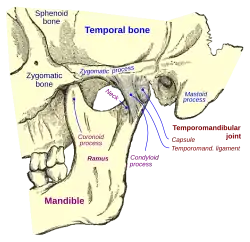

In anatomy, the temporomandibular joints (TMJ) are the two joints connecting the jawbone to the skull. It is a bilateral synovial articulation between the temporal bone of the skull above and the mandible below; it is from these bones that its name is derived. This joint is unique in that it is a bilateral joint that functions as one unit. Since the TMJ is connected to the mandible, the right and left joints must function together and therefore are not independent of each other.[1]

Structure

The main components are the joint capsule, articular disc, mandibular condyles, articular surface of the temporal bone, temporomandibular ligament, stylomandibular ligament, sphenomandibular ligament, and lateral pterygoid muscle.

Ligaments

There are three ligaments associated with the temporomandibular joints: one major and two minor ligaments. These ligaments are important in that they define the border movements, or in other words, the farthest extents of movements, of the mandible. Movements of the mandible made past the extents functionally allowed by the muscular attachments will result in painful stimuli, and thus, movements past these more limited borders are rarely achieved in normal function.

- The major ligament, the temporomandibular ligament, is actually the thickened lateral portion of the capsule, and it has two parts: an outer oblique portion (OOP) and an inner horizontal portion (IHP). The base of this triangular ligament is attached to the zygomatic process of the temporal bone and the articular tubercle; its apex is fixed to the lateral side of the neck of the mandible. This ligament prevents excessive retraction or moving backward of the mandible, a situation that might lead to problems with the joint.[5]

Each temporomandibular joint is classed as a "ginglymoarthrodial" joint since it is both a ginglymus (hinging joint) and an arthrodial (sliding) joint.[13] The condyle of the mandible articulates with the temporal bone in the mandibular fossa. The mandibular fossa is a concave depression in the squamous portion of the temporal bone.